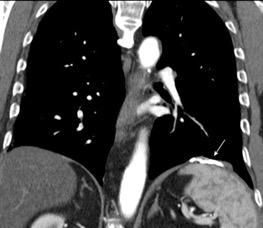

Tromboembolismo pulmonar.

Frecuencia del derrame:

Rx: 32%. TC: 47%

Unilateral. 85%

< 1/3 del hemitórax: 90%

Todos exudados

58% con eritrocitos

21% tabicación lo que causa demora en el diagnóstico

TEP. Empiema pleural. Atelectasia redonda

Porcel JM et al. Analysis of pleural effusions in acute pulmonary embolism: radiological and pleural fluid data from 230 patients. Respirology 2007/ Iguchi T et al. Desquamation of the subpleural lung parenchyma caused by empyema after pulmonary embolism: A case report. Respirol Case Rep. 2022 .

Derrame pleural 43-48% de pacientes con embolismo.

< 1/3 de hemitórax: 90%.(puede haber en lado opuesto).

Siempre exudados.

75% de los pacientes con TEP y derrame pleural tienen dolor pleurítico.